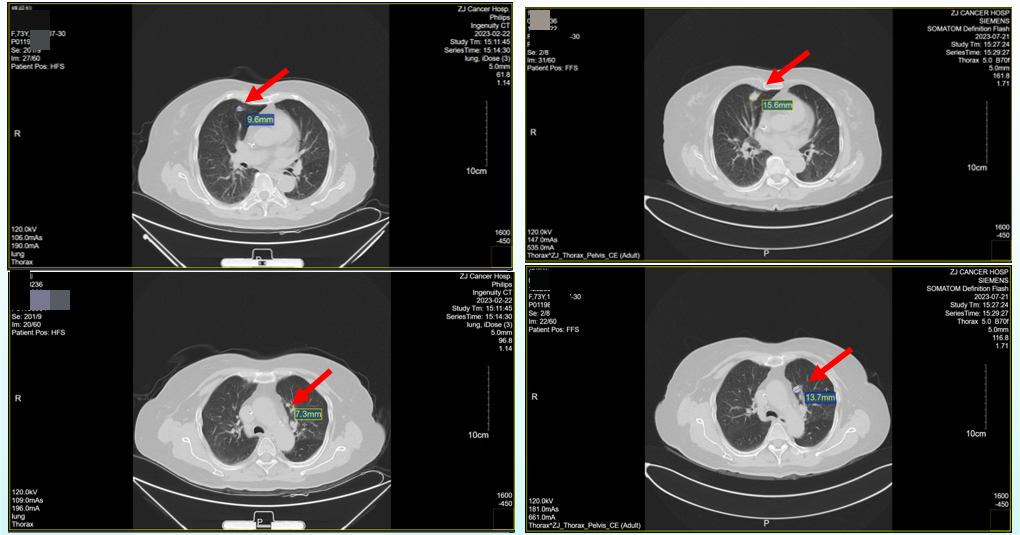

2023年7月21日复查胸、腹盆腔CT检查,提示对比(2023年2月22日)右肺中叶、左肺上叶转移瘤,较前增大。结肠癌术后改变,盆腔CT增强未见明显占位灶(图3)。